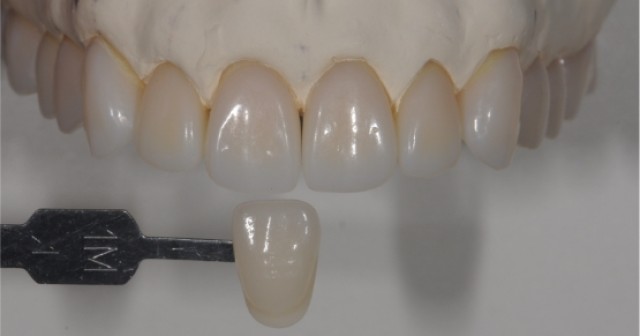

Using this tooth shade matching technique makes selecting a reference tooth shade easy, efficient, and predictable for restorative dentists chairside.